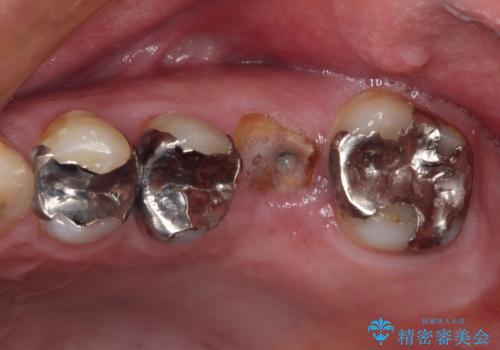

- 根っこの一部だけになった歯と咬むと痛みのある歯を気にして来院された患者様です。

上顎の歯根のみとなった歯は抜歯が必要であったので、抜歯を行い、インプラントあるいはブリッジのよる補綴治療を提案しました。

前後の歯は銀歯が装着されていたため、ブリッジによる補綴治療として、前後の歯もセラミックに置き換えることとしました。

下顎の根管治療がされた大臼歯は咬合時に痛みが認められたため、再度根管治療を行った後に補綴治療することとしました。